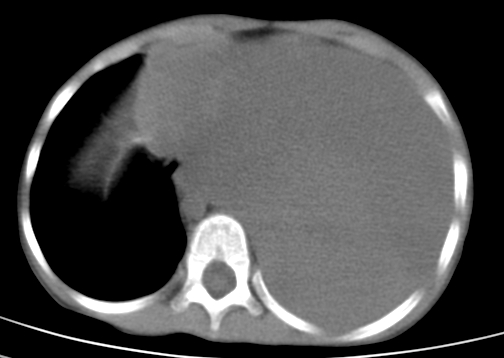

患儿 女 4岁,发热 咳嗽 胸透 考虑:左侧脓胸

左侧胸廓内见大量密实阴影,肺尖部尚有少量肺组织影,纵膈明显受压移位,肋骨未见明显受侵征象,虽然病人年龄较小,但如此大量的“积液”,还是要警惕,不同意一般感染,可结合穿刺脱落细胞学检查。

1)考虑左肺炎症感染。2)左侧大量胸腔积液。

1)考虑左肺炎症感染。2)未经穿刺只能定左侧大量胸腔积液。

左侧张力性大量胸腔积液压迫性肺不张、感染;建议治疗后复查。